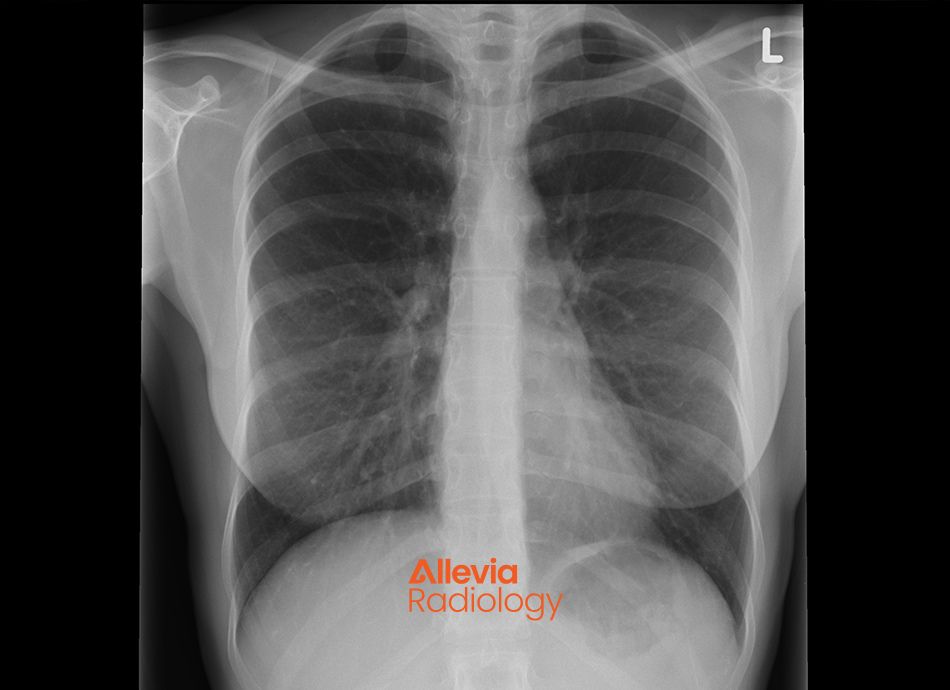

Allevia Radiology Chest X ray supplied

A chest X-ray uses a small amount of radiation to create an image that shows the ribs, lungs, diaphragm and size of the heart.

A chest X-ray is one of the most common x-rays to be taken. If you are acutely unwell with shortness of breath, fever and cough, a chest X-ray may be ordered to look for signs of infection, (such as pneumonia), inflammation, fluid build up in the lungs or tumours or masses.

It's also often used to assess people who have smoked for many years to look for signs of chronic lung disease and lung cancer.

A chest X-ray is also often done before an operation in older adults to check the lungs and heart appear normal.